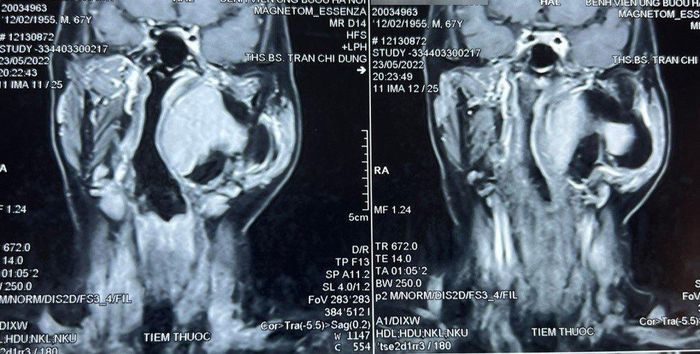

Hình ảnh chụp cộng hưởng từ khối u khoảng bên họng của bệnh nhân

Trước đó, bệnh nhân đến khám vì khối sưng phồng vùng mang tai trái, ngoài ra không kèm theo khó chịu gì. Qua thăm khám và đánh giá, bác sĩ phát hiện một khối u lớn vùng cổ kích thước khoảng 10 x 8 cm, thuộc khoảng bên họng, trải dài từ nền sọ xuống hạ họng, đẩy lệch thành bên họng vào trong, gồm 2 phần: phần nông nằm dưới tuyến mang tai và phần còn lại nằm sâu hơn.

Chẩn đoán sơ bộ ban đầu khối u là lành tính, ranh giới không rõ ràng. Thông qua hội chẩn các bác sĩ quyết định tiến hành phẫu thuật sớm lấy bỏ khối u tránh nguy cơ khối u chèn ép vào đường thở, đường ăn, thần kinh, mạch máu và các thành phần liên quan khác.